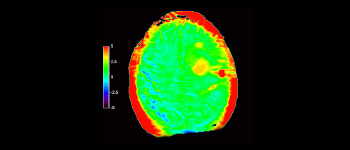

Astrocytoma

Brain astrocytoma, post-radiotherapy

with 3D APT